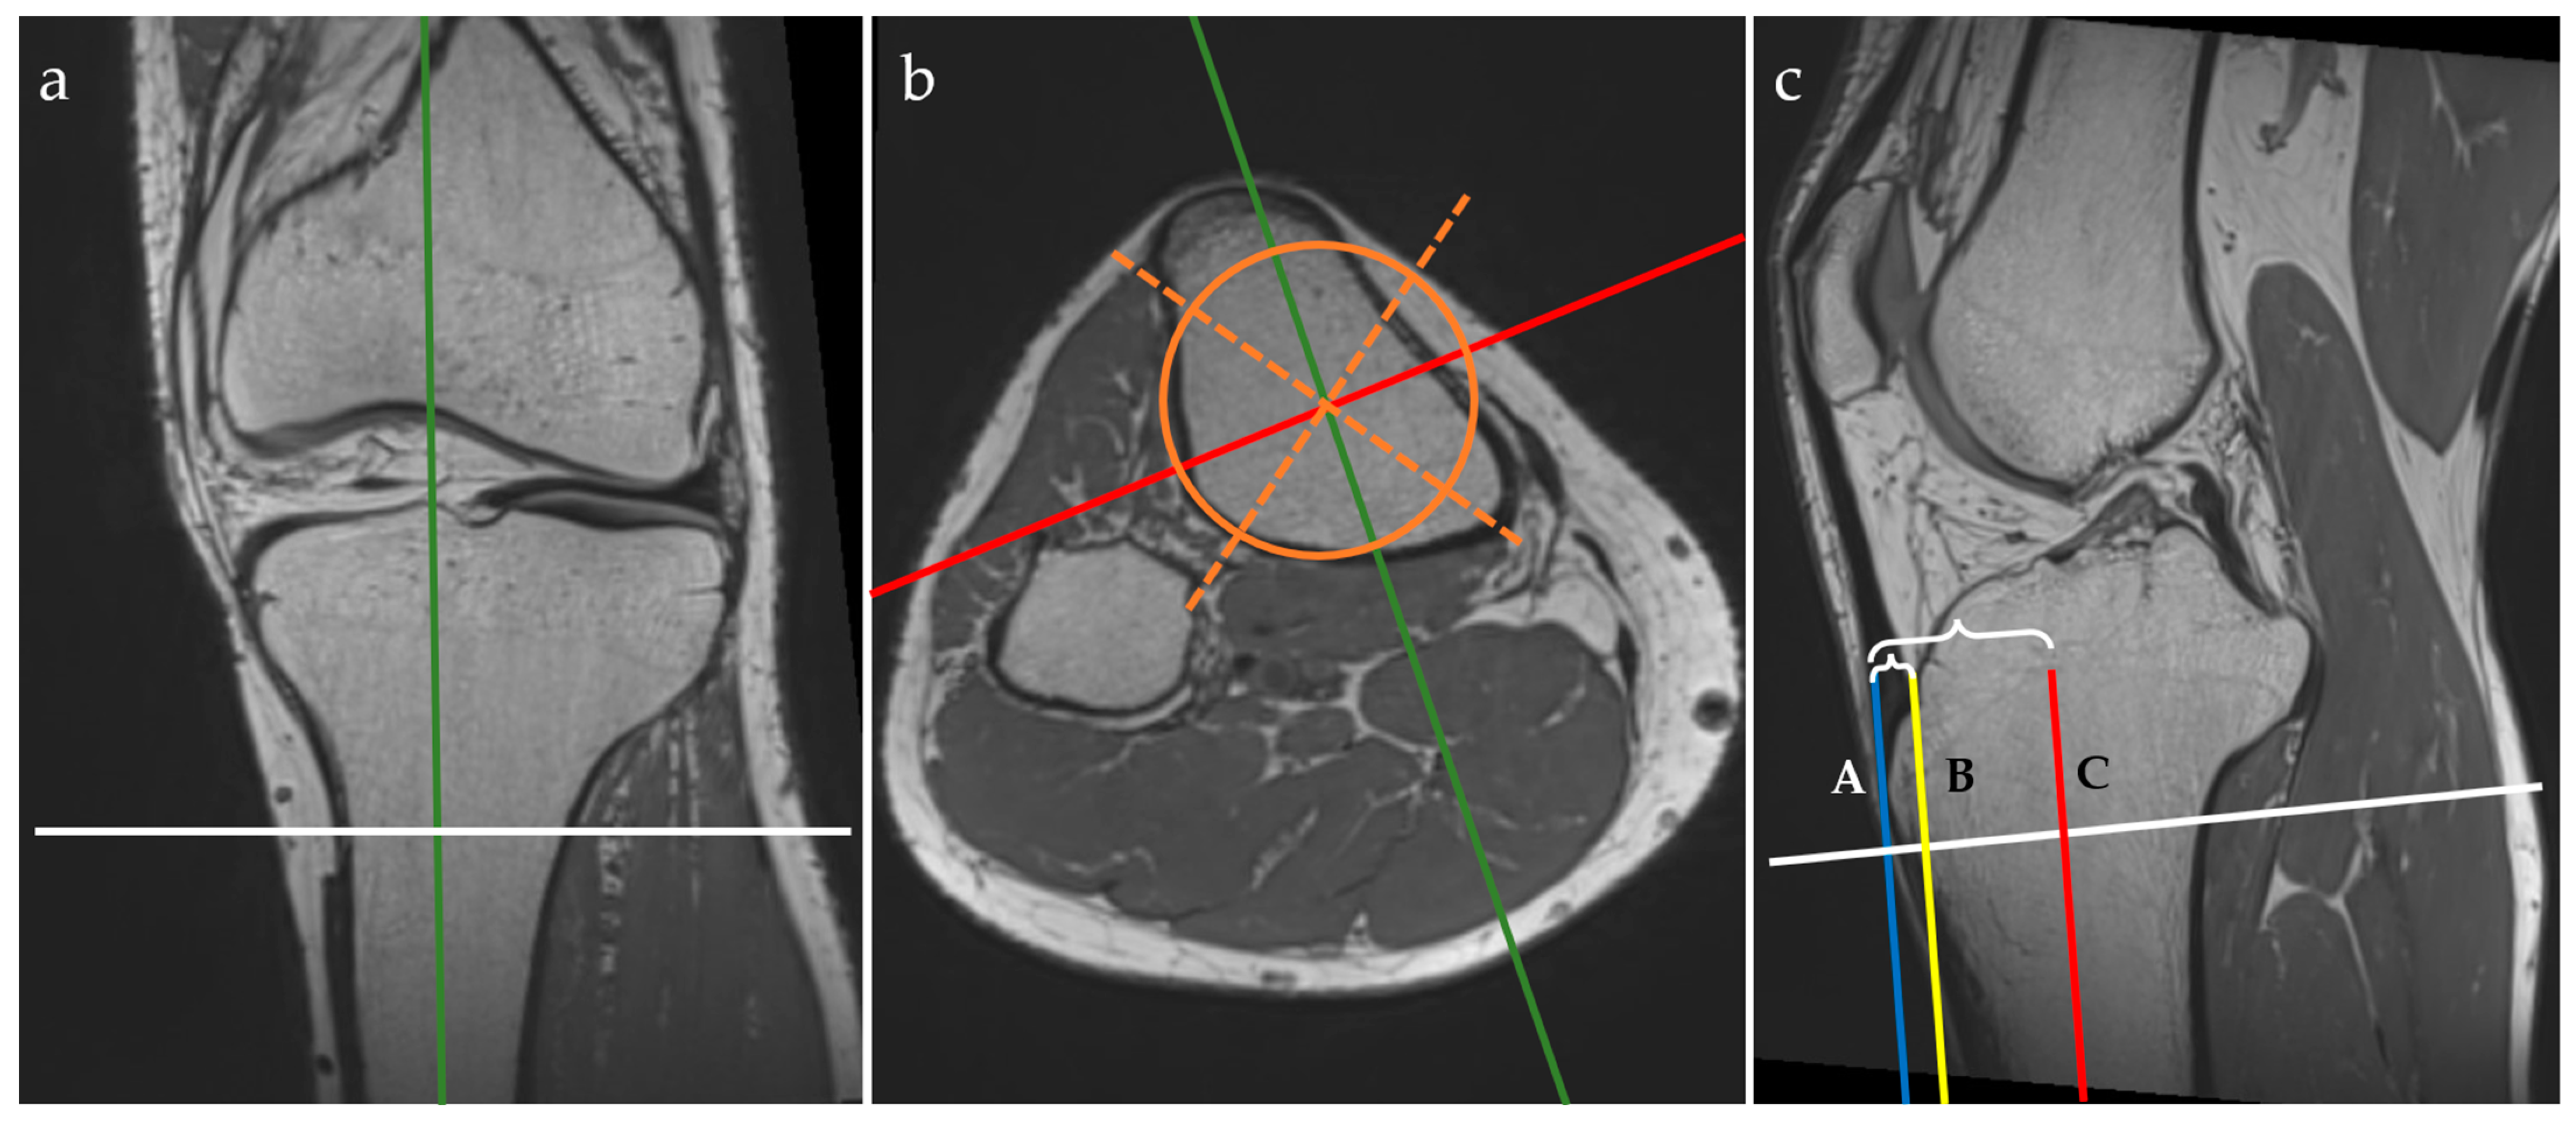

All MRI examinations were performed with a Magnetom Vida 3T machine (Siemens, Munich, Germany) using the dedicated knee MRI protocol of the Department of Radiology and Medical Imaging within the “Foisor” Clinical Hospital of Orthopaedics, Traumatology and Osteoarticular TB. The knee examinations were performed with the dedicated knee coil (TxRx Knee 18) with the patients positioned supine, feet first. The studied knee was immobilized with positioning sponges and sand bags while the contralateral knee was placed on top of a dedicated support. All patients benefited from a 3D PD-weighted isovolumetric sequence acquired in the sagittal plane (resolution = 0.5 × 0.5 × 0.5 mm, TR = 1200 ms, TE = 33 ms, flip angle = 120 degrees, bandwidth = 422 Hz/Px, and scanning time = 5 min and 31 s), which is part of the routine knee protocol in our department. The postprocessing was performed using the multiplanar reformatting (MPR) view mode of the console software, where the actual measurements were taken, as in the example in Figure 1.

Figure 1.

Three-plane view of multiplanar reformatting in the coronal (a), axial (b), and sagittal (c) planes of the 3D PD isovolumetric acquisition and graphical overlay representation of the MRI protocol for the anterior tibial tuberosity index (ATTI) assessment. The lines represent the following: tibial midline sagittal plane (green), coronal plane through the middle of the tibia (red, C), axial plane (white), geometric tibial axes (orange dotted lines) and area (orange circle). Tangent lines through the tuberosity of the anterior tibia (blue line, A), and through the epiphyseal line of the anterior tibial cortex (yellow line, B). Distances between A and B, and A and C, respectively, are marked with accolades.

On the MPR view, landmarks were drawn as follows:

- on the coronal plane: we aligned the vertical axis with the middle of the tibial shaft and the horizontal axis parallel with the epiphyseal line and passing through the maximum point of the tibial tuberosity;

- on the axial plane: we aligned the axes with the middle of the tibial shaft (both the sagittal and coronal axes) by drawing a circle that fitted the cross-section of the tibial shaft and attempted to overlie the posterior cortical line while covering the maximum surface, then drawing two intersecting lines within the circle to find the geometrical center; the sagittal axis was then rotated to pass through the maximum point of the tibial tuberosity;

- on the sagittal plane: we aligned the horizontal axis with the epiphyseal line.

When using the MPR view, the three planes (i.e. coronal, axial, and sagittal) were orthogonal. The next steps were to draw vertical lines, as follows:

- we identified the most prominent point of the tuberosity of the anterior tibia and drew a vertical line tangent to this point—the blue line (A);

- we identified the anterior tibial cortex at the level of the epiphyseal line and drew another vertical line tangent to this point—yellow line (B);

- these two vertical lines must be parallel to the vertical axis that passes through the middle of the tibial shaft—the red line (C).

We measured the distances between these three lines to obtain the anterior tibial tuberosity index (ATTI) and we calculated the ratio between them, dividing the distance between A and B by the distance between A and C (i.e. (AB)/(AC)). This represents a transposition of the method for measuring the anterior tibial tuberosity index on the lateral radiographs of the knee, as described by Visuri et al. [3,12].